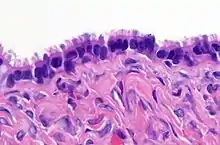

| High magnification micrograph of a Brenner tumor, a type of surface epithelial-stromal tumor. H&E stain. | |

Brenner tumor

Brenner tumors are uncommon surface-epithelial stromal cell tumors in which the epithelial cell (which defines these tumors) is a transitional cell. These are similar in appearance to bladder epithelia. The tumors may be very small to very large, and may be solid or cystic. Histologically, the tumor consists of nests of the aforementioned transitional cells within surrounding tissue that resembles normal ovary. Brenner tumors may be benign or malignant, depending on whether the tumor cells invade the surrounding tissue.